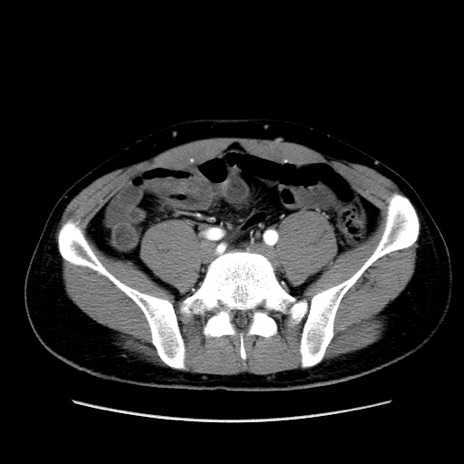

症例36(横断像)

【症例】20歳代 男性

【主訴】心窩部痛

【現病歴】今朝より上腹部痛あり。一旦軽快していたが再度出現したため救急要請。昨日夕に白身の魚を含む刺身を食べた。

【身体所見】BP 136/89mmHg、HR 74/min、BT 37.0℃、腹部:膨満、軟、心窩部に圧痛あり。反跳痛なし、筋性防御なし、腸雑音やや亢進あり。

【データ】WBC 17700、CRP 0.48